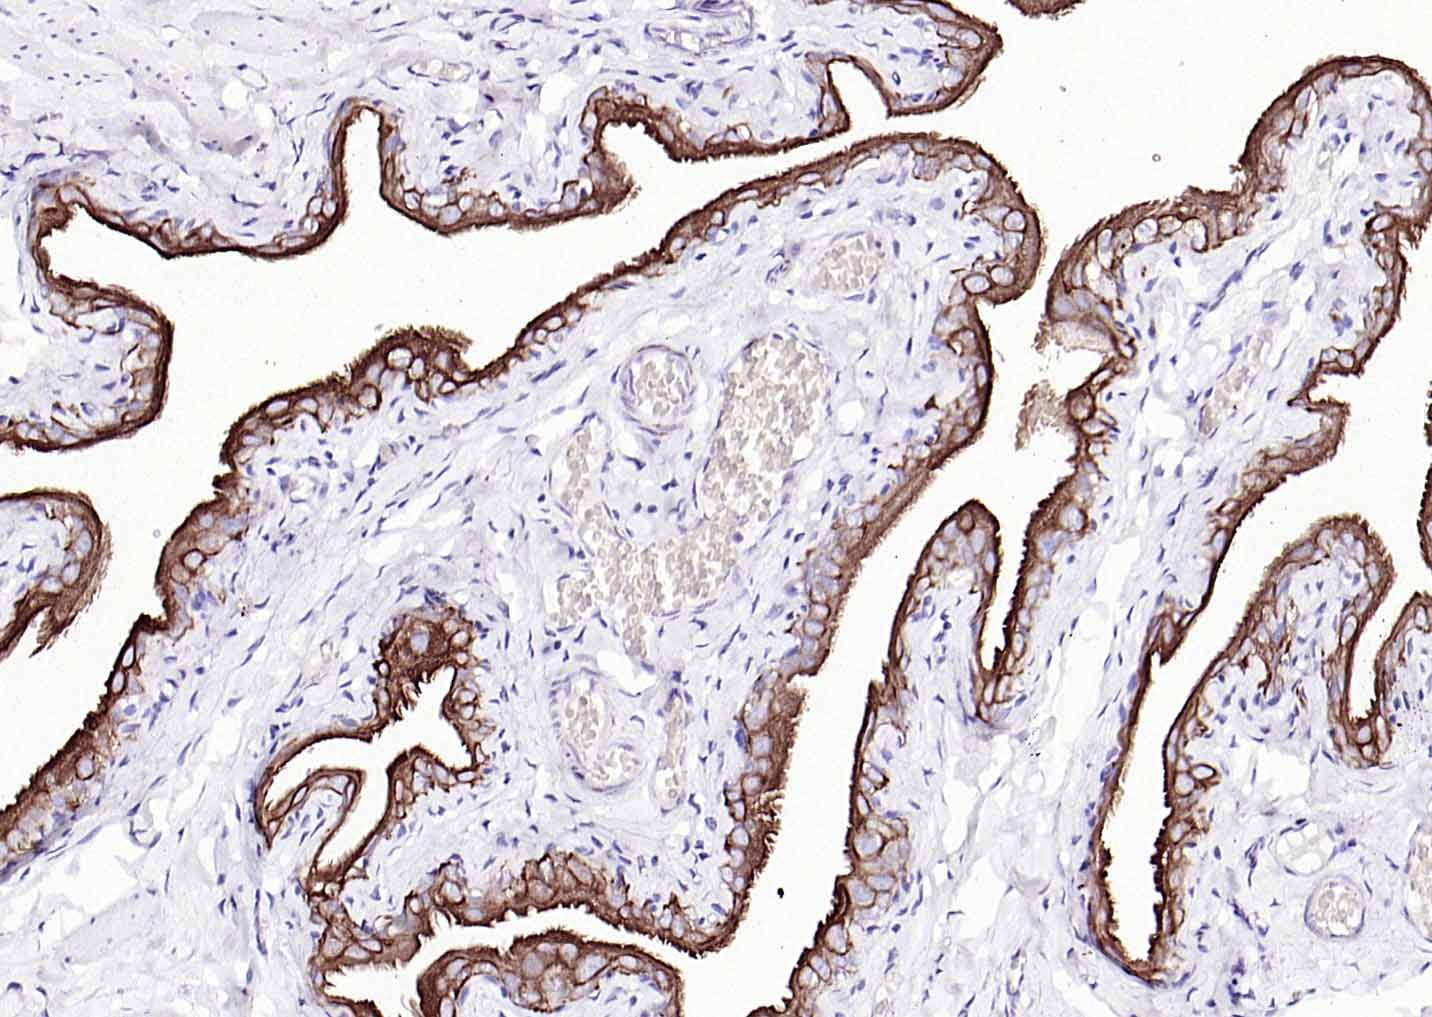

Vimentin is a developmentally regulated intermediate filament protein (IFP) found in cells of mesenchymal origin. It is believed to be involved with the intracellular transport of proteins between the nucleus and plasma membrane. Unlike other IFP proteins, vimentin is expressed, along with desmin, during the early stages of cellular development. During the development process, vimentin is exchanged for new, tissue-specific IFPs. Vimentin has been implicated to be involved in the rate of steroid synthesis via its role as a storage network for steroidogenic cholesterol containing lipid droplets. Vimentin phosphorylation by a protein kinase causes the breakdown of intermediate filaments and activation of an ATP and myosin light chain dependent contractile event. This results in cytoskeletal changes that facilitate the interaction of the lipid droplets within mitochondria, and subsequent transport of cholesterol to the organelles leading to an increase in steroid synthesis.

| IHC-P | Human, Mouse, Rat | 1:100-500 | |